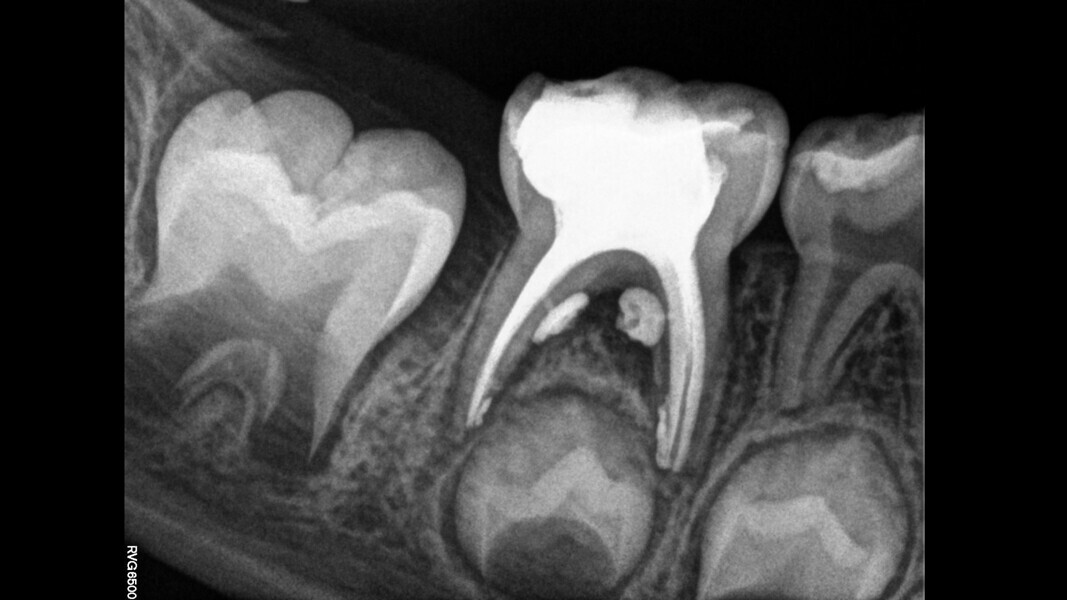

Case 4 (Figs. 14–18)

This male patient was 4 years and 6 months old and presented with constant and spontaneous pain of the mandibular left first primary molar that had lasted for several days but no facial oedema or buccal gingival swelling. Deep decay was observed but no mobility or deep probing depths. On the radiograph, the carious lesion could be seen to be compromising the pulp chamber and initial bone damage was observed in the septal area. Pulpectomy was the treatment of choice. In the removal of the carious lesion, the pulp was exposed and no bleeding was observed. Pulp necrosis was diagnosed. Two mesial and two distal canals were located, and the tooth was obturated. At a second appointment, the tooth was asymptomatic and was restored with a stainless-steel crown. At the 30-month control, the tooth presented no symptoms and a normal eruptive process was observed on the radiograph.